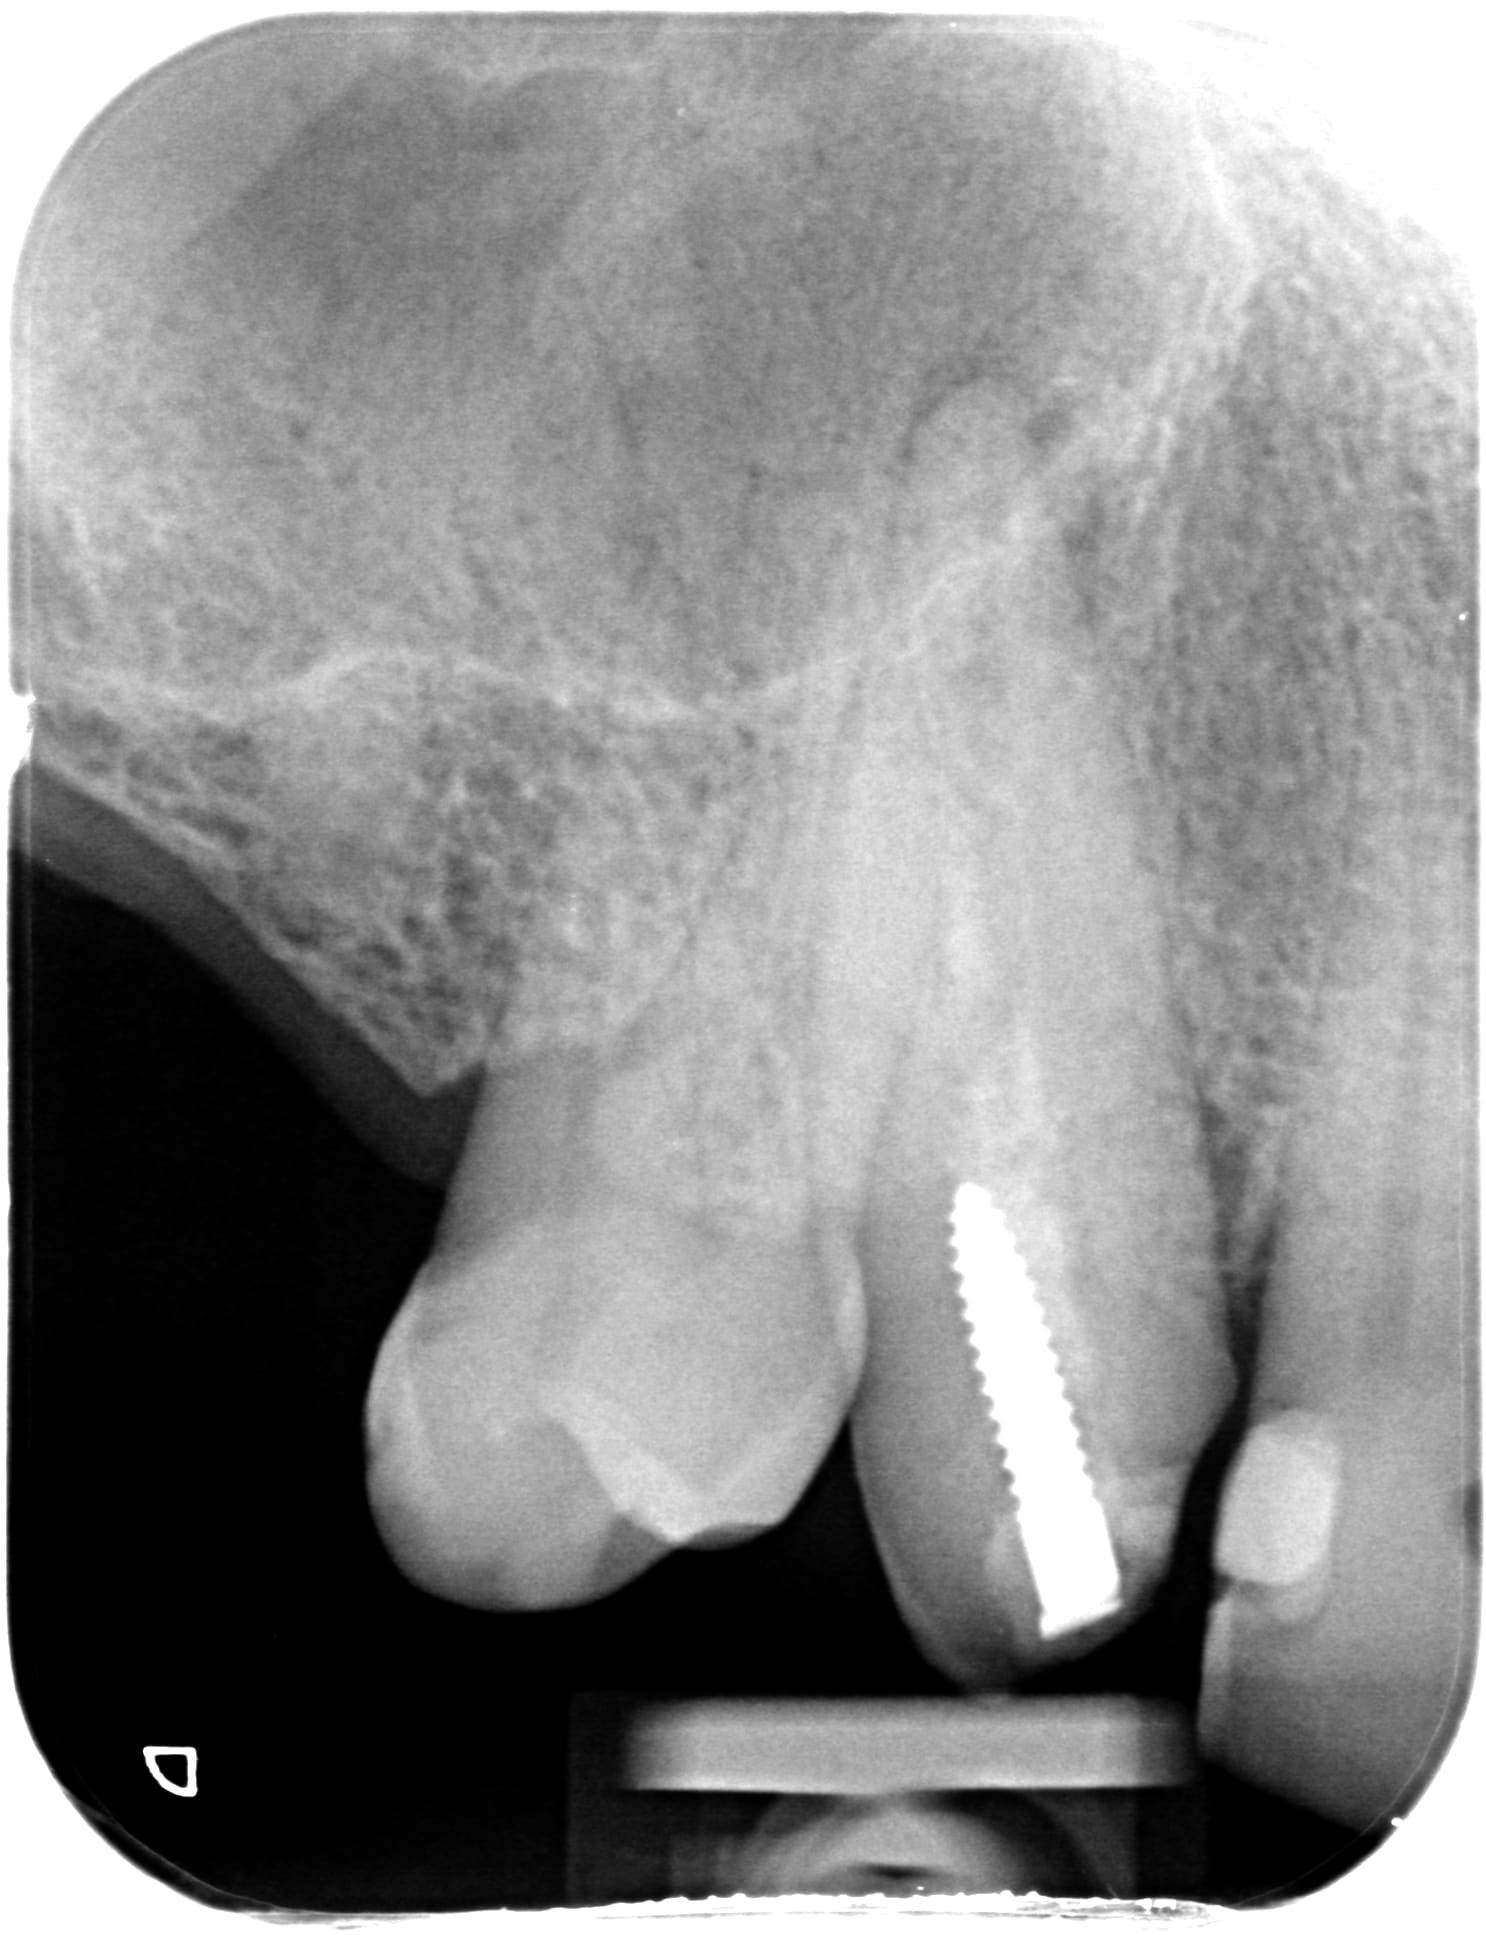

moi je fais tout bien mes controles... et c'est vrai que la priorité c'est la qualité des radios. (j'en ai des bien mieux mais je retrouve plus le dossier...)

488 x 20171031 143047 x0raxcqieext 4 hoprxn - Eugenol

1536 x 20170912 185521 xxps5fdi7wv  4 zqtipo - Eugenol

1570 x 20171104 093932 xryufeigfwma 3 bnuqdo - Eugenol

1825 x 20180814 173735 xkh4f3zz8djs 4 fuedvz - Eugenol